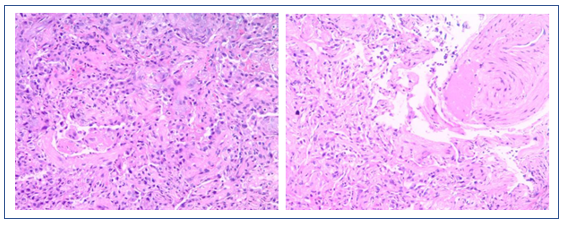

2019年1月11日,行肺组织活检、肺泡灌洗液培养。肺泡灌洗液和痰培养出多重耐药肺炎克雷伯菌、产吲哚金黄杆菌(多次)、曲霉菌、木糖氧化无色杆菌。淋巴细胞CD系列计数,T淋巴细胞和B淋巴细胞总数均下降。复查自身抗体:全阴性。

患者1月4-6日使用激素,然后停用,胸部CT显示部分病变加重,部分病变被吸收;另外,中下肺背部实变比较明显,而且气管和支气管征比较突出,另外,病变沿着气管、支气管束的分布,符合机化性肺炎表现。但是机化性肺炎不能引起类似呼吸衰竭如此严重的情况,所以个人考虑是否为纤维素性机化性肺炎(AFOP),当然需要病理诊断来进一步明确。患者淋巴细胞非常低,这是目前很难解释的,所以还是期待进一步的检查。

进一步检查结果

病理提示肺泡腔内有纤维球突入,是否考虑为AFOP的病理特征。该患者淋巴细胞水平下降,免疫功能差。即使为AFOP,也可能是继发于血液系统疾病、严重感染等疾病,AFOP仅为“果”,而非“因”。